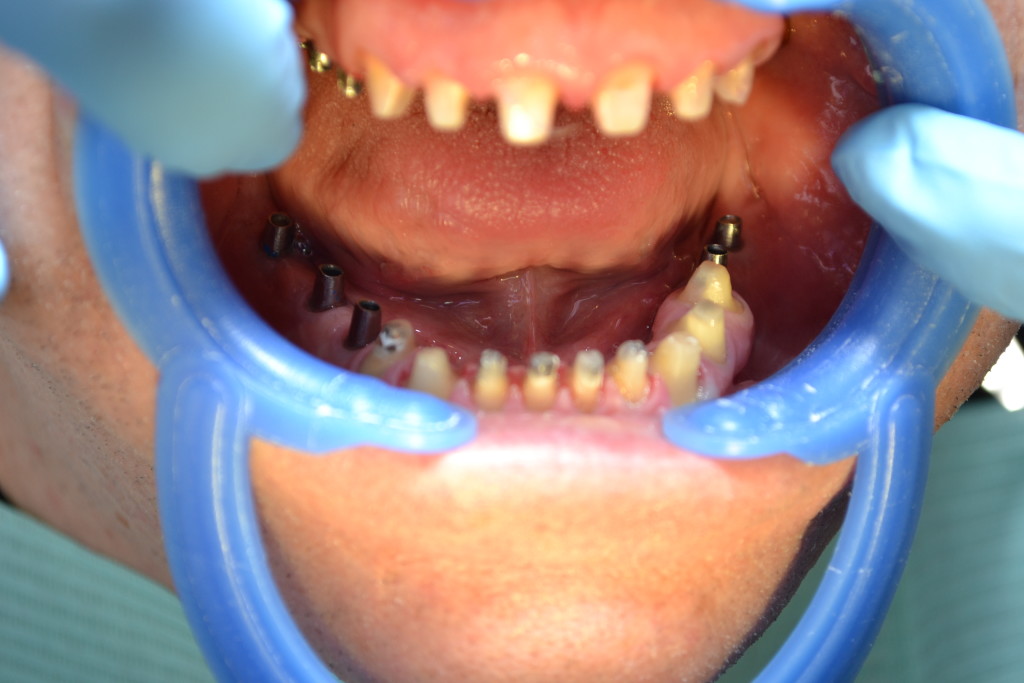

- начинаем установку имплантов:

- имплантация зубов:

- вживленные имплантаты